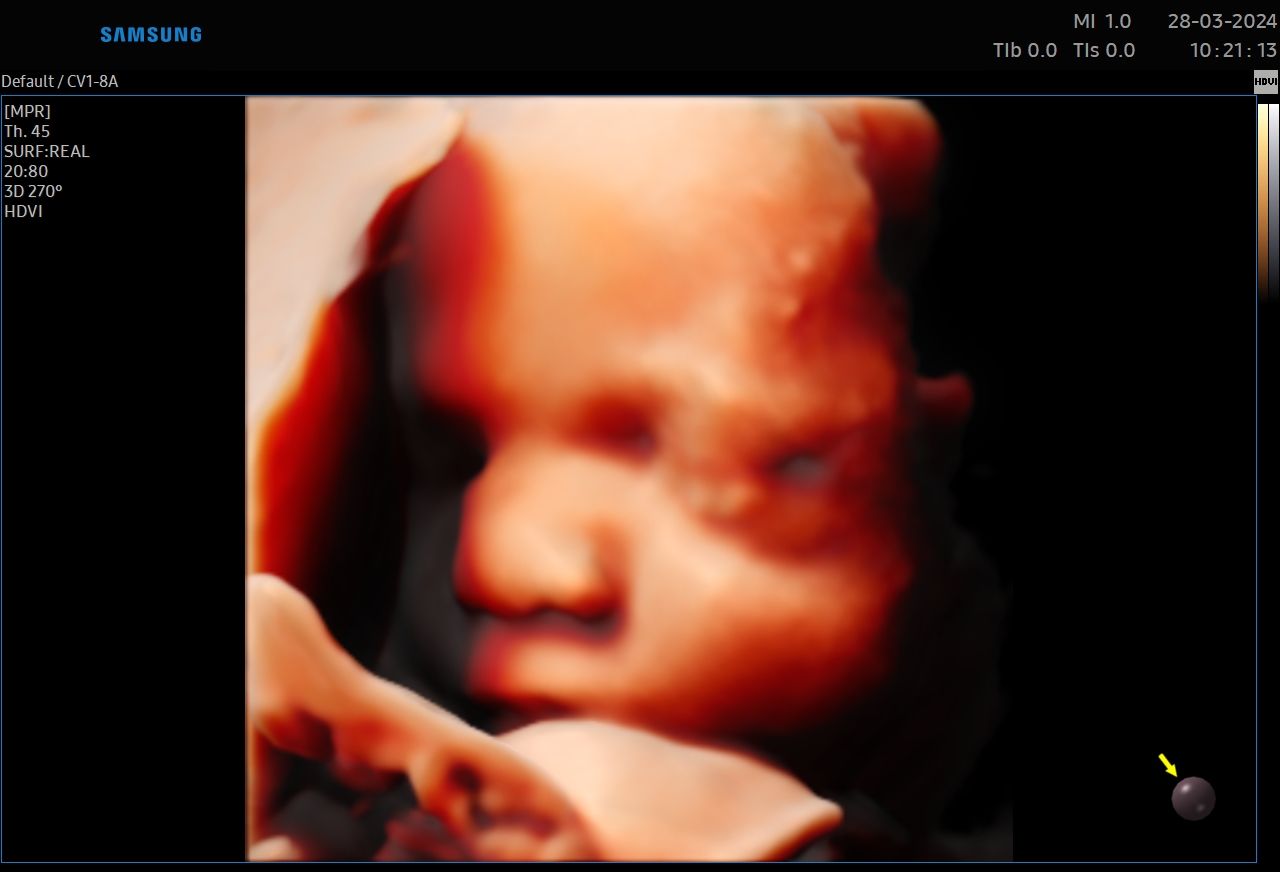

CERTYFIKAT BADAŃ PRENATALNYCH POLSKIEGO TOWARZYSTWA GINEKOLOGÓW I POŁOŻNIKÓW

CERTYFIKAT BADAŃ PRENATALNYCH FMF ( FETAL MEDICINE FOUNDATION - LONDYN )

W ramach praktyki wykonuję pełen zakres badań ultrasonograficznych w zakresie ginekologii jak i położnictwa wraz z badaniami prenatalnymi , badaniami ultrasonograficznymi piersi .

Zdjęcia i filmy